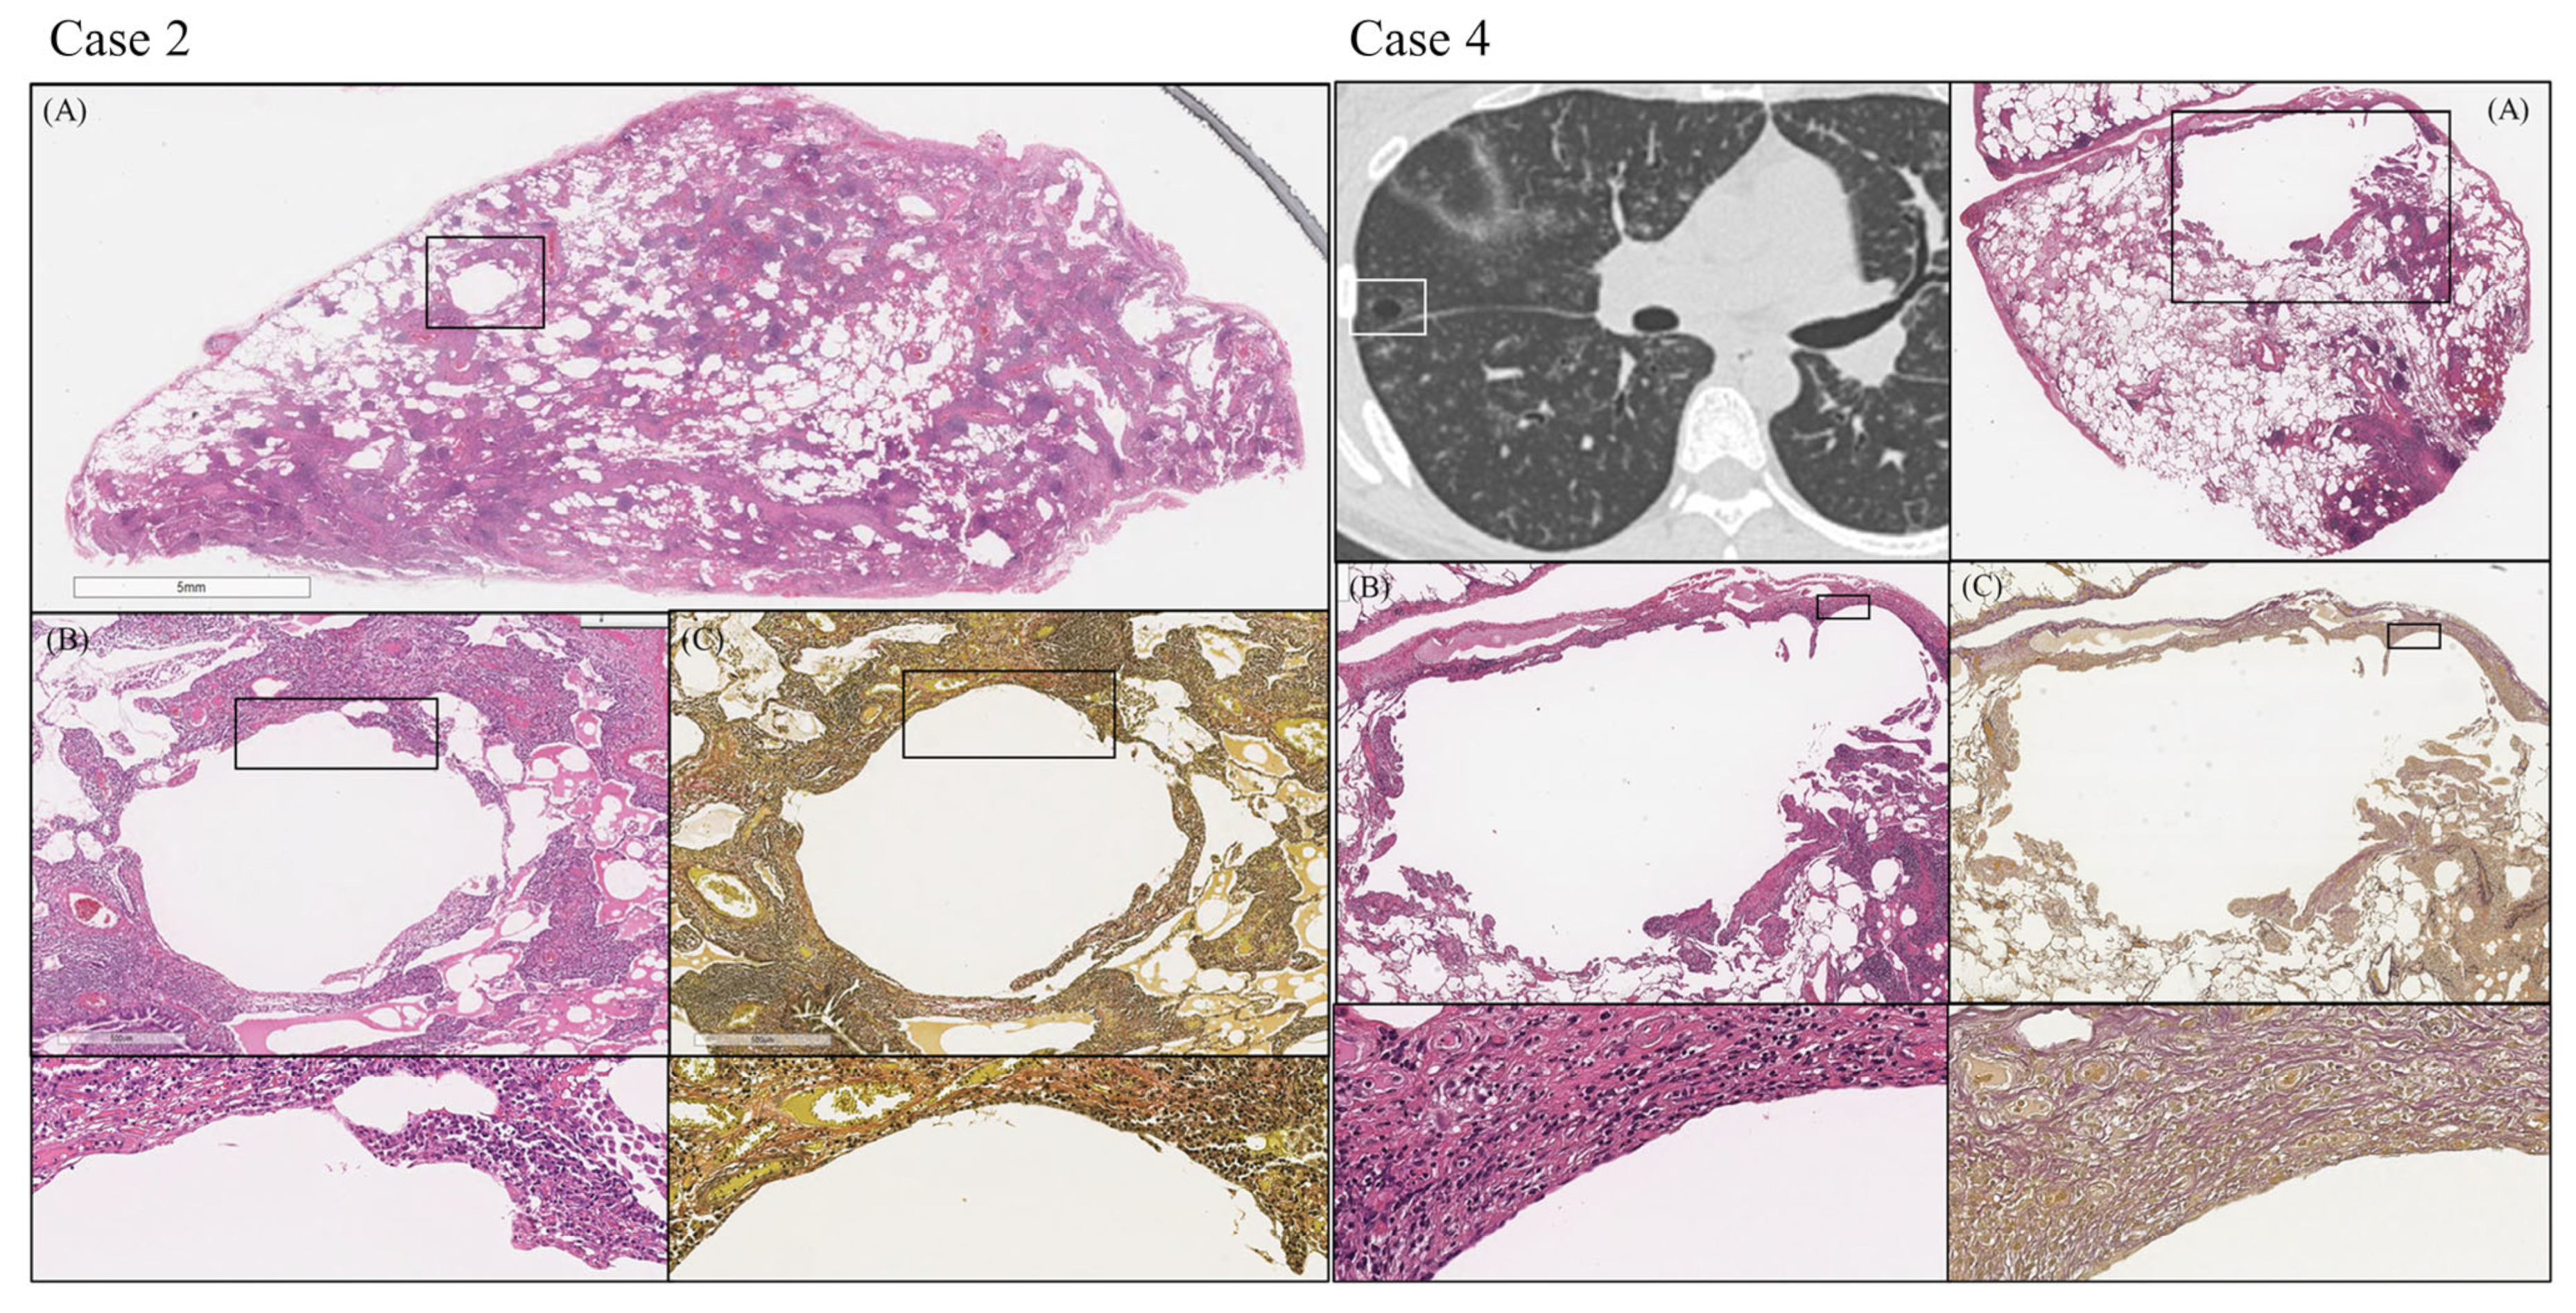

| Pathological Findings | n = 8 |

|---|---|

| Type (Hypervascular/ Mixed/ Plasmacytic) | 0/0/8 |

| Distribution | |

| Bronchovascular bundle (Grade 0/1/2/3) | 0/0/7/1 |

| Interlobular septa (Grade 0/1/2/3) | 0/3/3/2 |

| Alveolar wall (Grade 0/1/2/3) | 0/5/0/3 |

| Fibrosis (Grade 0/1/2/3) | 1/5/2/0 |

| Cell infiltration | |

| Plasma cell (Grade 0/1/2/3) | 0/0/0/8 |

| Lymphoid follicles with germinal center (Grade 0/1/2/3) | 0/4/2/2 |

| Eosinophils (Grade 0/1/2/3) | 3/4/1/0 |

| Characteristics of cyst wall | n = 4 |

| Prominent infiltration of plasma cells | 4 (100%) |

| Prominent infiltration of macrophages | 0 (0%) |

| Granuloma | 0 (0%) |

| Opening of bronchi | 4 (100%) |

| Loss of elastic fibers | 4 (100%) |